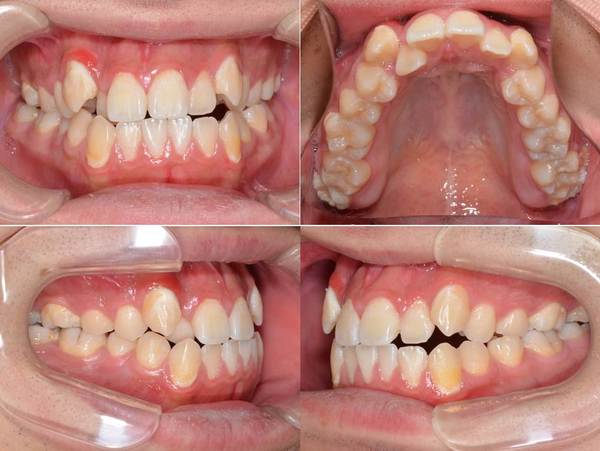

歯列のデコボコが気になる。 ハーフリンガル 上下小臼歯抜歯

上の歯のデコボコがきになる

上顎前歯部叢生

18歳

上顎:カスタムメイド型リンガルブラケット矯正装置

下顎:唇側マルチブラケット装置

上顎:右側5番・左側4番

下顎:右側4番・左側5番

約9か月

約824,000円